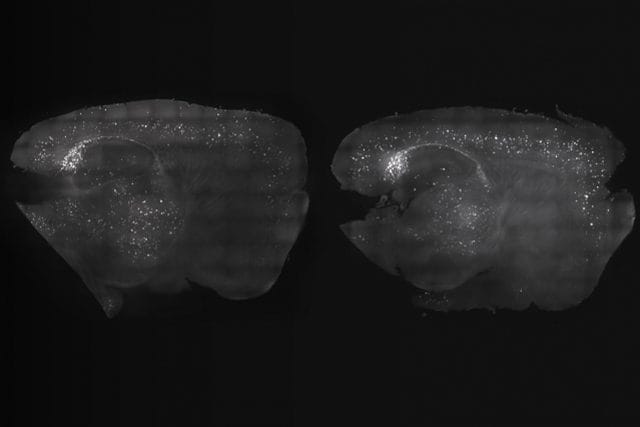

L'esperimento. Gli scienziati, coordinati dal professor Li-Huei Tsai, direttore presso l'istituto di Cambridge, hanno basato i propri test sui risultati ottenuti da precedenti indagini. Tsai e colleghi, infatti, nel 2016 avevano dimostrato che, stimolando il cervello dei topi affetti dal modello murino dell'Alzheimer con una luce stroboscopica a 40 Hertz, venivano rimosse sia le placche di beta amiloide che i grovigli di proteina tau, inoltre veniva catalizzato il processo di eliminazione dei rifiuti ad opera delle cellule di microglia. Tuttavia i benefici riguardavano la sola corteccia visiva, senza offrire vantaggi mnemonici e cognitivi, che rappresentano il principale obiettivo del trattamento della demenza. Per questo nei nuovi esperimenti hanno deciso di aggiungere la stimolazione acustica, anch'essa con onde a 40 Hertz. La procedura si basa sull'attività dei neuroni, che originano segnali elettrici in grado di sincronizzarsi a specifiche frequenze, e che risultano alterate nei pazienti colpiti da demenza. Attraverso la stimolazione acustica Tsai e colleghi hanno osservato una riduzione delle proteine dannose anche nella corteccia uditiva e nell'ippocampo, una parte del cervello coinvolta nella memoria.

Risultati eccezionali. I benefici maggiori sono stati ottenuti combinando la stimolazione visiva a quella acustica, che ha determinato una riduzione ancor più marcata delle placche di beta amiloide, anche nella corteccia prefrontale del cervello. I benefici fisiologici si sono subito riflessi sulle capacità mnemoniche e cognitive dei topi trattati, che sono risultati molto più bravi a ricordare oggetti e percorsi del classico labirinto sperimentale. Sebbene i risultati siano stati ottenuti sui topi, Tsai e colleghi sono ottimisti sul fatto che simili trattamenti possano essere efficaci anche sugli esseri umani. Anche se richiedono di essere somministrati con costanza, dato che gli effetti sui modelli murini sono risultati meno evidenti a una settimana dalla sospensione del trattamento. I dettagli della pionieristica ricerca sono stati pubblicati sull'autorevole rivista scientifica Cell.